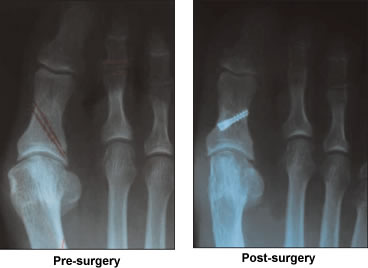

By summer, 2003, I noticed a "bump" on the side of my right foot; my big toe was starting to cross under the second toe. I went to an orthopedic surgeon who told me that he couldn't remove the bunion. The only procedure he could do, as a last resort, involved removing the joints, but I would no longer be able to work. He referred me to a local podiatrist who gave me a cream to rub on and inserted pads between the toes to separate them. She gave me instructions to come back in five weeks for the pads to be replaced. No one knew how to help or knew of anyone who could. The pain continued to get worse even through the nights.

My wife's internet research on bunions and treatment found Dr. Leavitt, his website and email address. My wife wrote and the next day had a response from him. A short time later with MRI films and X-rays in hand, we were in his office. He knew the cause of the problem; the procedure needed to correct it and told me what the long recovery would involve. He told me to think it over as it was major reconstructive surgery, but I knew it was my only option. The procedure was done on November 18, 2004. I followed directions during my recovery period to the letter and beginning on March 2005, I returned to work pain free.